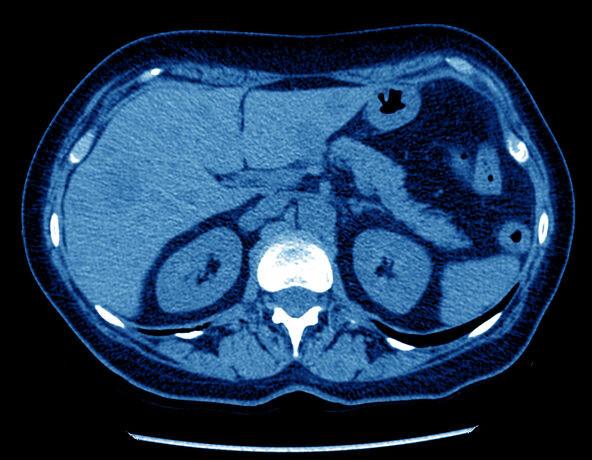

تعتبر الأشعة التداخلية من المجالات المتقدمة في الطب، حيث تتيح للأطباء الحصول على صور دقيقة تساعد في تشخيص الأمراض وعلاجها تتنوع التقنيات المستخدمة في هذا المجال، وسنستعرض فيما يلي أبرز هذه التقنيات:

يُعتبر التصوير بالأشعة السينية واحداً من أقدم وأكثر التقنيات استخداماً في الأشعة التداخلية تعتمد هذه التقنية على إرسال شعاعات سينية تمر عبر الجسم وتُسجل على فيلم أو جهاز رقمي تتيح هذه الصور للأطباء رؤية الهياكل الداخلية للجسم، مما يساعد في تحديد وجود أي تشوهات أو أمراض تُستخدم الأشعة السينية بشكل واسع في تشخيص الكسور، الأورام، وأمراض الرئة، وتتميز بسرعة الحصول على النتائج

التصوير بالموجات فوق الصوتية

يستند التصوير بالموجات فوق الصوتية إلى استخدام الموجات الصوتية عالية التردد لإنشاء صور للأعضاء الداخلية تتميز هذه التقنية بأنها غير مؤلمة وآمنة، مما يجعلها خياراً شائعاً لتشخيص الحالات المختلفة، خاصة خلال فترة الحمل تُستخدم الموجات فوق الصوتية لتقييم القلب، الكبد، الكلى، والأعضاء الأخرى، فضلاً عن الكشف عن الأورام والالتهابات كما تُستخدم في بعض الإجراءات العلاجية، مثل سحب السوائل أو توجيه الإبر بدقة